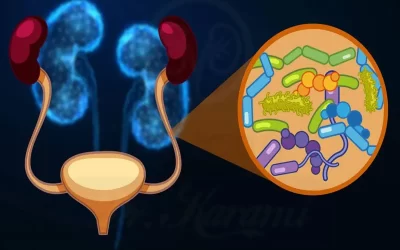

ساده ترین درمان عفونت ادراری در خانم ها

یکی از مشکلات شایع در بین جوانان ساده ترین درمان عفونت ادراری در خانم ها می باشد که به سیستیت ماه عسل شناخته شده می باشد. این عفونت معمولا در شروع یا بعد از مقاربت ایجاد می شود. این موضوع بخصوص برای خانم ها نگران کننده است. علائم عفونت ادراری در...